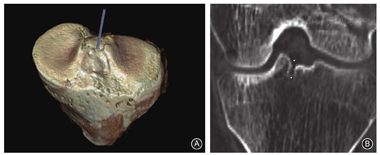

5份新鲜完整标本(车祸1例,肿瘤4例),按照标准解剖流程,显露胫骨髁间隆突,观察胫骨髁间隆突孔的存在,观察与周围结构的关系、推测其功能;行CT扫描三维重建对该孔进行定位(图1)。采用HE染色对胫骨髁间隆突孔的具体位置、周围结构、与周围组织关系、近端覆盖情况进行观测,对小孔内容物组织、孔口孔壁及孔底组织进行组织学分析,并使用亚甲蓝自孔口滴入孔道,直观观察孔道内及周围组织浸润情况。

孔道及周围CT值测量结果示,按CT值大小排列:孔口(472.5±30.1)HU>孔壁(312.3±22.5)HU>孔底(202.4±17.3)HU>孔内(118.3±10.4)HU>孔口覆盖物(75.0±11.1)HU(图1)。

CT引导下在髁间隆突中凹处使用直径≤1 mm的针头可轻易探到孔道,进针深度与孔道深度基本一致。可见孔口位于髁间隆突中凹处、前后叉韧带止点之间,周围区域与骨质仅有一薄膜间隔。HE染色显示孔口周围为软骨,孔道中部孔壁及孔底为松质骨,孔内容物为较致密结缔组织,孔道口覆盖物为滑膜(图3,图4)。